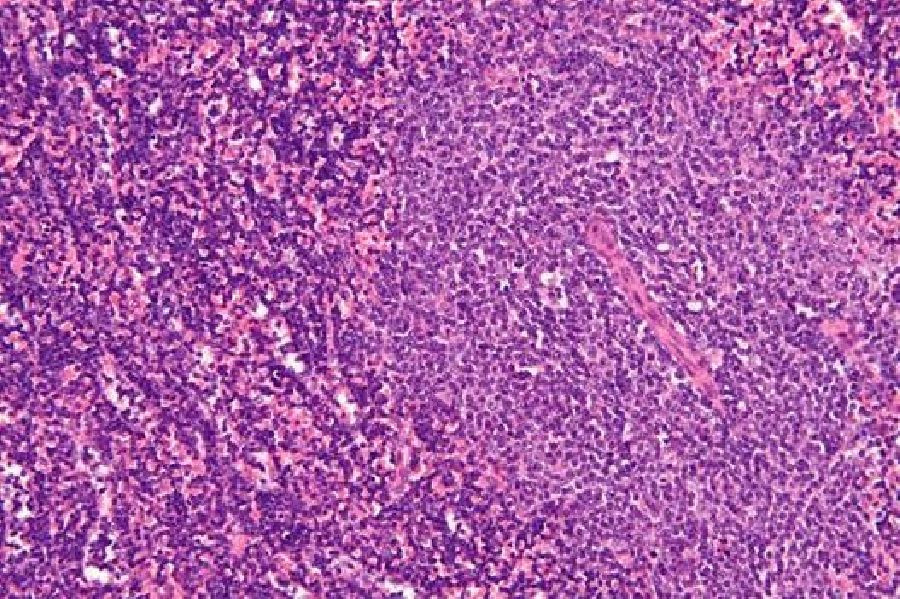

Descubren un gen causante de la leucemia linfocítica crónica, presente en más del 80% de los pacientes

El hallazgo, publicado en la revista 'Molecular Cancer', muestra que más del 82% de los pacientes con esta patología expresan niveles altos del gen RRAS2 y que las cantidades más altas de presencia del mismo se relacionan con leucemias más agresivas.